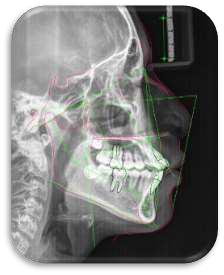

Revisiones Bibliográficas que sinteticen el conocimiento actual sobre técnicas de imagen (periapical, panorámica, lateral, cefalometría, CBCT) y su aplicación clínica.

Fotografiasintrayextraoralesparaortodoncia Cefalometrias